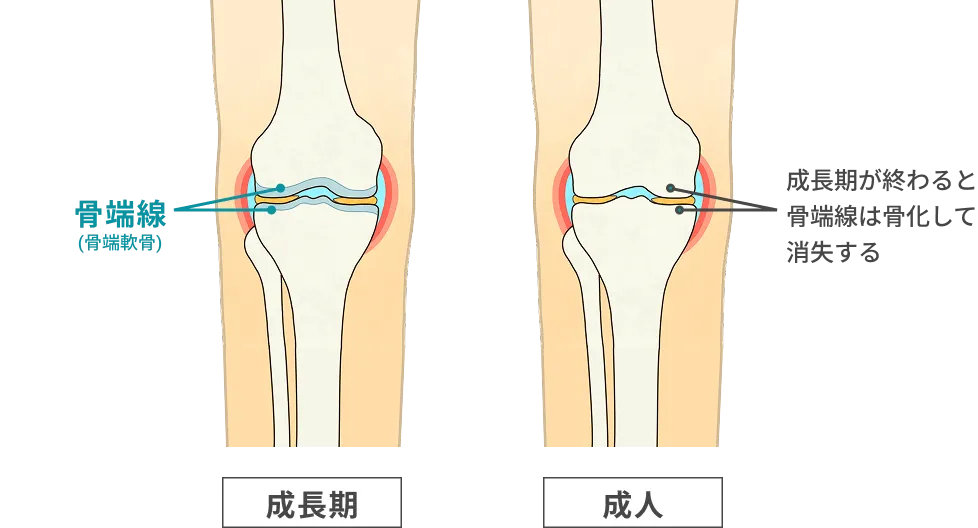

子供の骨は骨端線という箇所の軟骨組織が成長することで伸びていきます。

残念ながら骨年齢が16歳になると骨端線が閉じてしまい、どれだけ治療をしてもそれ以上身長は伸びません!

また骨年齢=実年齢ではありません。16歳未満だからといってまだ身長が伸びるとは限らないのです。

伸びにくくなるのは事実です。性ホルモンが⾻端線を閉ざしてしまう働きがあるので身⻑が伸びにくくなるのも事実です。